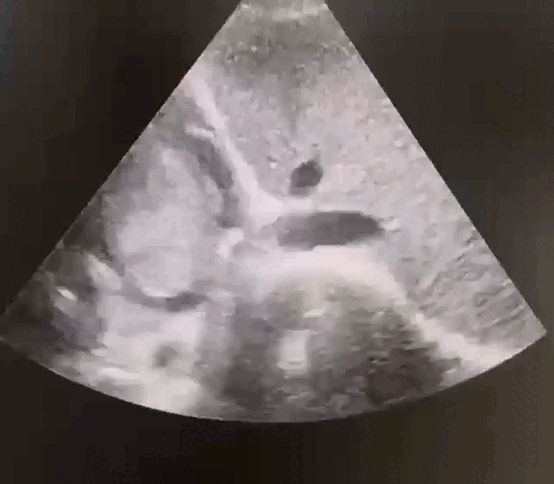

该患者右心房内的粘液瘤已达10cm×6cm×4cm大小,几乎填满了整个右侧心腔,并且随着心脏的跳动一次次向着更深的部位挪动,若不紧急手术,等待患者的可能是心衰、肺栓塞、猝死等意外。

术前心脏彩超显示心腔里随心脏跳动的肿瘤